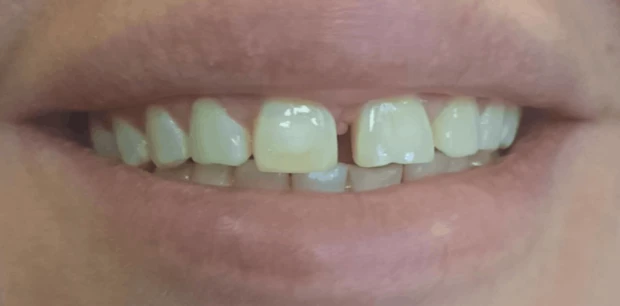

Реставрация, отбеливание

Эстетическая реставрация центрального зуба

Пациент Р., 20 лет обратился с жалобами на эстетическую неудовлетворенность из-за скола центрального зуба. Проведена эстетическая реставрация композитным светоотверждаемым пломбировочным материалом.